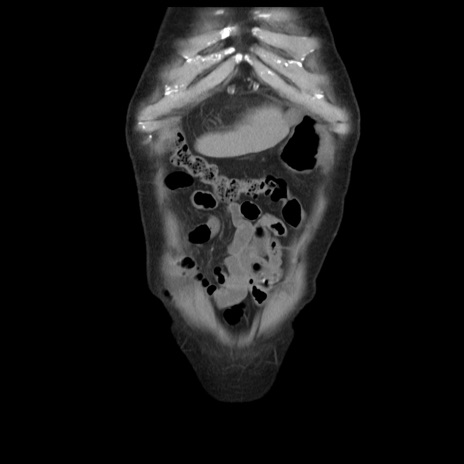

横断像

【症例】70歳代男性

【主訴】腹痛

【現病歴】肝硬変・肝細胞癌にてかかりつけの方。約9時間前に食後より腹痛出現。症状が徐々に増悪し、嘔吐出現したため来院。

【既往歴】肝硬変、肝細胞癌(RFA、TACE後)

【身体所見】意識清明、表情苦悶様、BT 36℃、BP 129/78mmHg、P 88bpm、SpO2 97%(RA)、右上腹部から心窩部にかけて圧痛あり、反跳痛なし、筋性防御あり。

【データ】WBC 5800、CRP 0.16